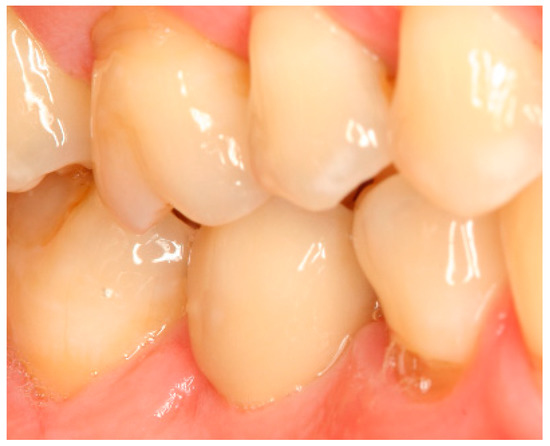

Figure A20.

Clinical situation at the 3-year follow-up. Lateral view.

Figure A21.

Radiograph of the perimplant bone situation at the 3-year follow-up. Compared to the 1-year follow-up, relatively stable bone situation.